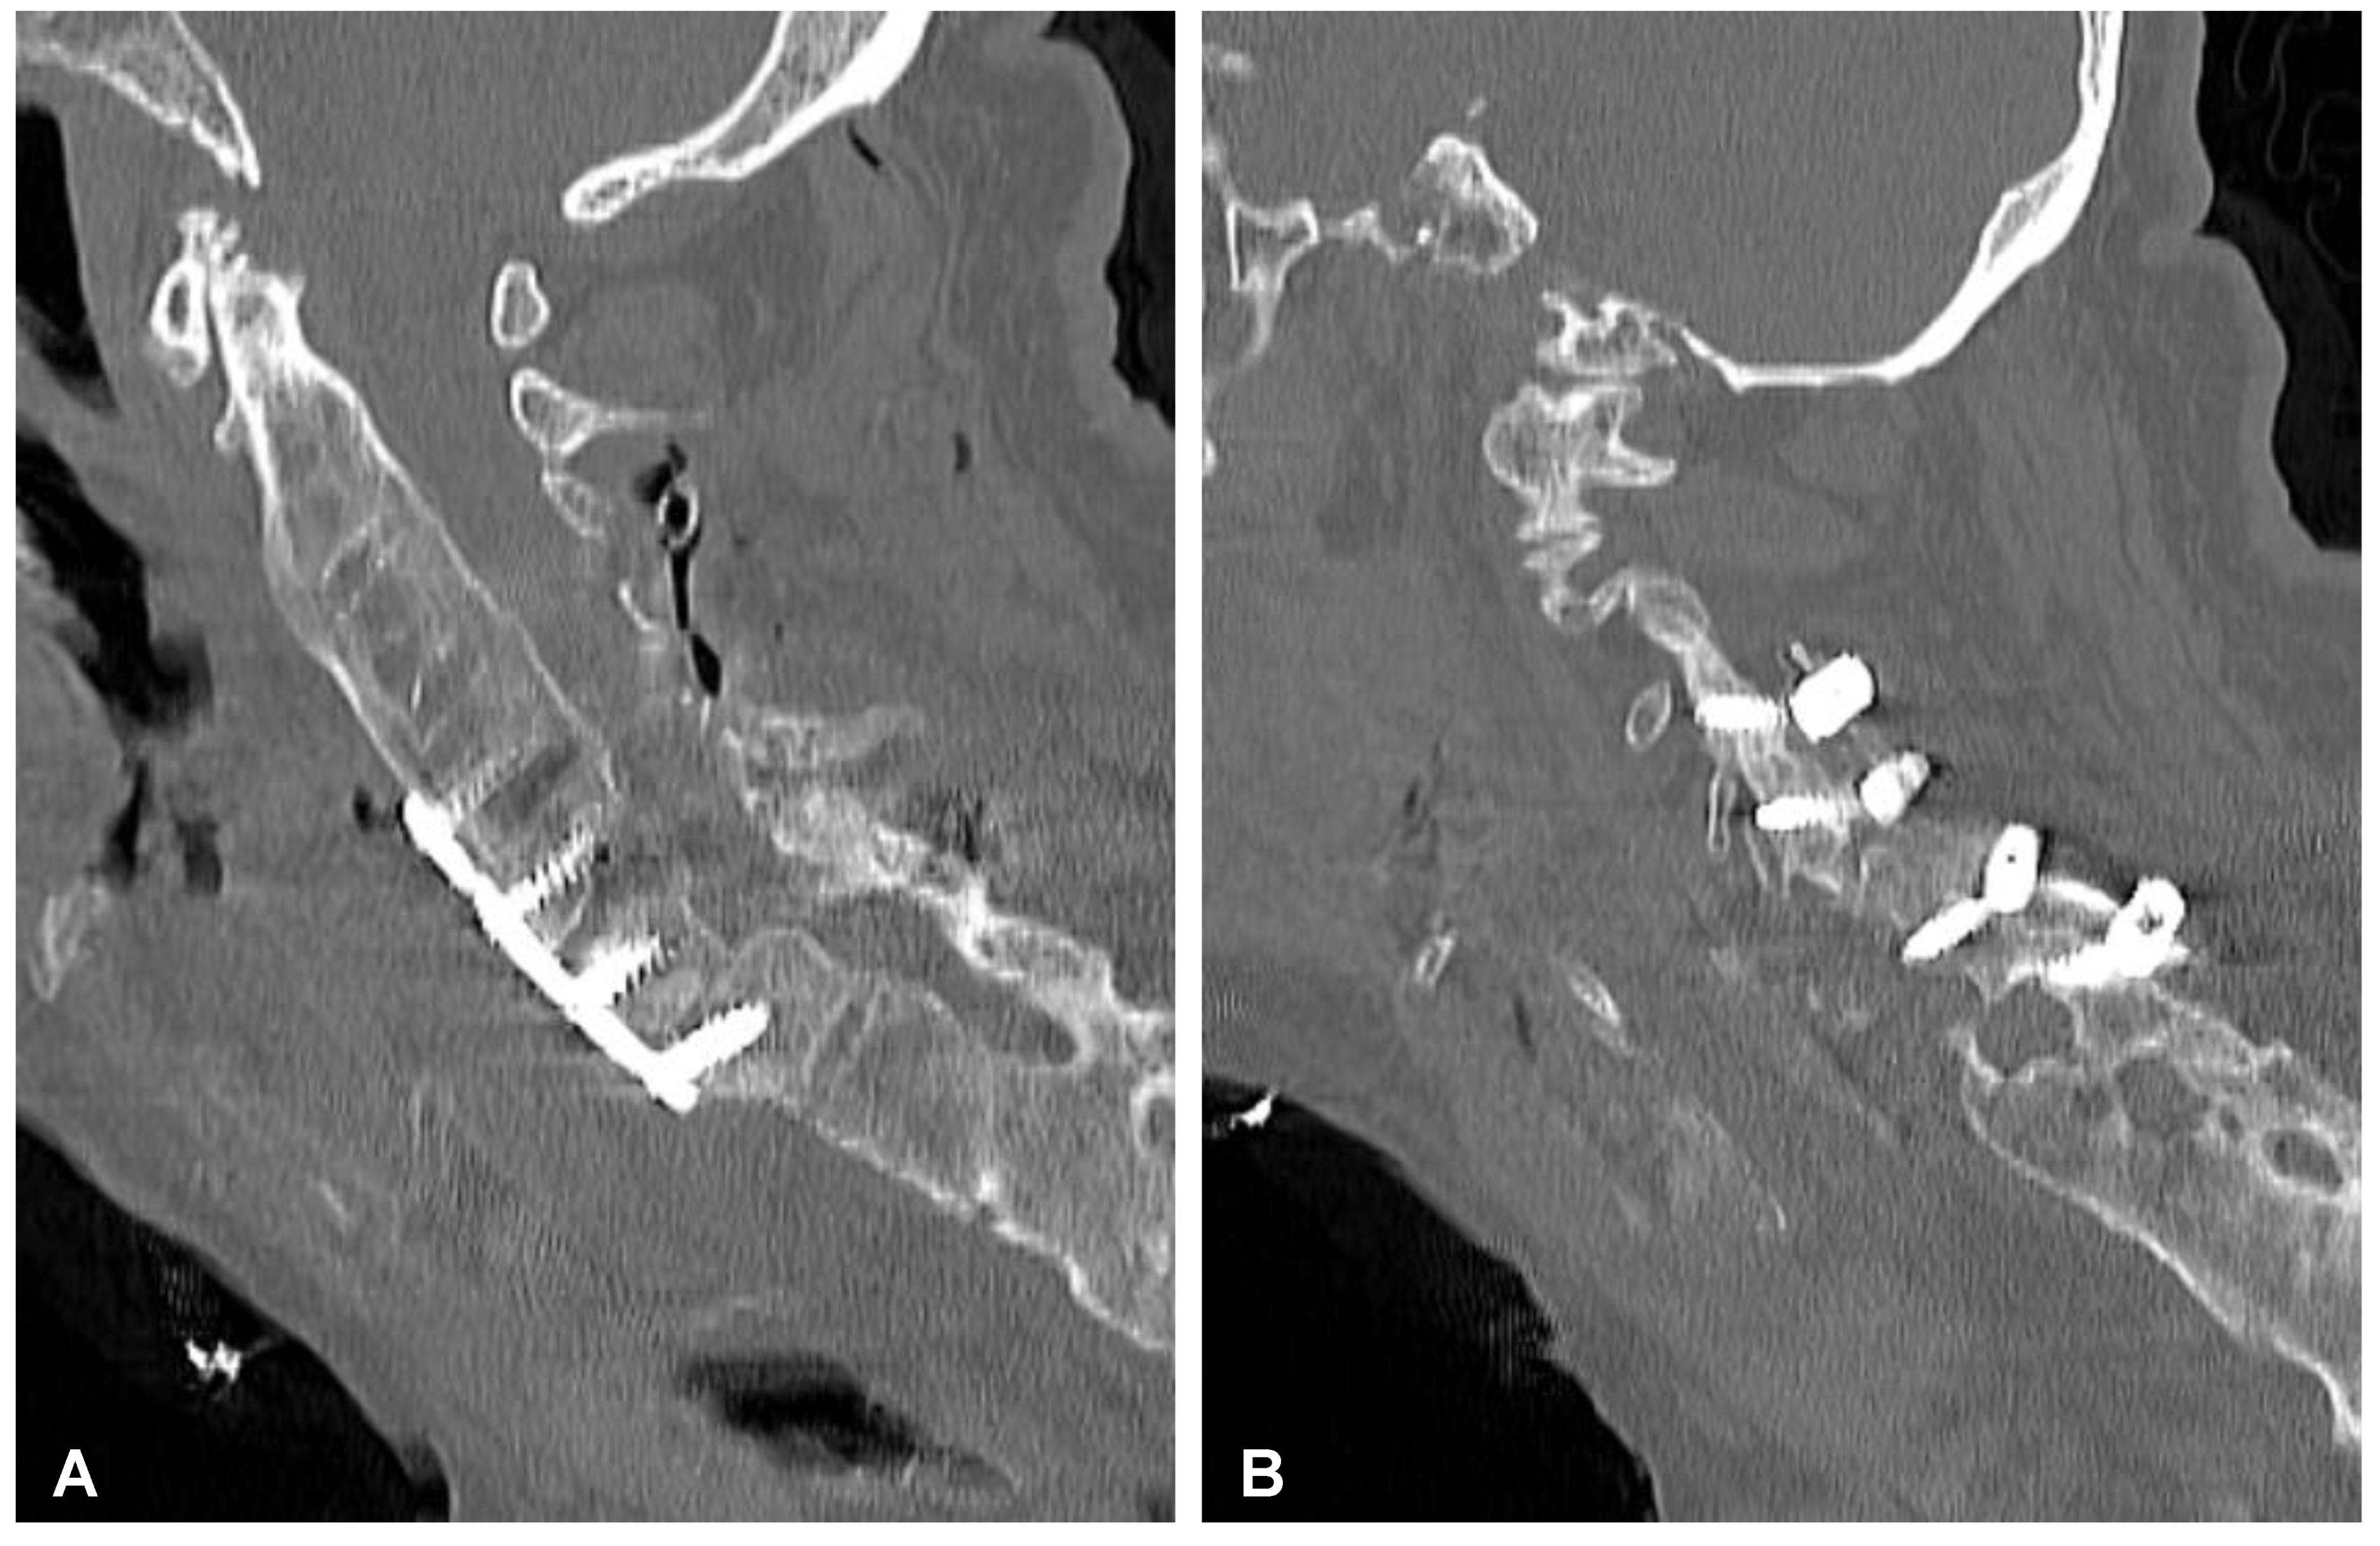

After initial diagnostics and preparations, the patient was transferred to the operating room. The posterior percutaneous transpedicular stabilization at the L2-L3-L5-S1 levels (Mantis; Stryker, Kalamazoo, MI, USA) with cement augmentation (VertaPlex HV; Stryker, Kalamazoo, MI, USA) for each inserted screw (4 mm × 6.5 mm/50 mm; 4 mm × 6.5 mm/45 mm) under intraoperative 2-dimensional (2-D) fluoroscopy control was performed in the first stage of surgery. In the second stage of surgery, from a lateral approach, the left side of the retroperitoneal cyst was emptied, and watery/light yellow fluid similar to urine was obtained. Therefore, a distractible vertebral body replacement implant (AsterX; Medtronic, Minneapolis, MN, USA) was placed between the L3 and L4 bodies with the placement of a retroperitoneal precutaneus Redon drainage system. A control CT scan performed one day after the operation revealed the correct placement of all the implants (Figure 5 and Figure 6). The second CE-CT scan performed two days after surgery consecutively showed evidence of post-traumatic right ureteral injury, urine leakage, and hydronephroureter (Figure 7). The general examination of intraoperatively obtained fluid revealed the following results: pH: 9.0; protein: 600 mg/dL; transparency and color before centrifugation: sanguine and cloudy; transparency and color before centrifugation: transparent and dark yellow; absolute leukocytes (LEU): 1197 cells/μL; and sediment: single round epithelium in the sample with erythrocytes loosely cover the field of vision (15–20 in the counterfield). The microbial culture of the intraoperative obtained fluid after 7 days was negative. After 4 days, the patient was transferred to another local hospital specializing in urological care. Due to the overall late presentation covering advanced hydronephrosis, ureteric stricture formation, and non-functional kidney, the nephrectomy and ureter ligation were performed. After urological treatment, the patient has been on follow-up for 2 years with no evidence of neurological or urological problems.

Figure 5. Postoperative sagittal CT scans (non-contrast enhanced) after the two-stage surgery of the lumbar spine demonstrating placement of the distractible vertebral body replacement implant between L3 and L4 (A) and posterior percutaneous transpedicular stabilization at the L2-L3-L5-S1 levels (B).